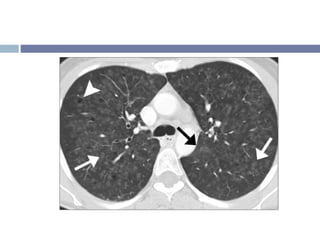

Nódulos centrilobulares Vidrio despulido

• #13 a) Nódulos centrilobulares: Sag MIP muestra nodulos centrilobulares (flechas) y patrón en árbol en yema (cabeza de flechas). Note q los nódulos se acercan pero no contactan la pleura, consistente con una distribución centrilobular. b) Opacidades en vidrio despulido multifocales y bilaterales en una Hg Pulmonar. Se ve mejor en el pulmón derecho.